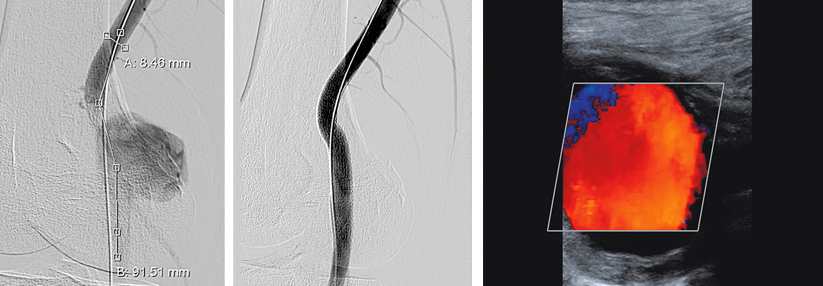

Dass die Patientin ein Paradebeispiel für eine nicht-lehrbuchmäßige Präsentation einer KHK darstellt, zeigt sich auch bei den Untersuchungen im Marienhospital. EKG und Echo bleiben bis auf eine diskrete Vorderwandhypokinesie unauffällig, auf dem Ergometer kann sie nicht ausbelastet werden. Insgesamt ergibt sich eine Vortestwahrscheinlichkeit für eine stenosierende KHK von unter 6 %. Trotzdem entschließen sich die Kollegen dazu, die 41-Jährige zu katheterisieren – und entdecken eine subtotale Hauptstammstenose.

Die gute retrograde Kollateralisierung, die sich im Verlauf (acht Jahre ohne adäquate Ischämiediagnostik!) gebildet hat, bewahrte die Patientin vermutlich vor einem akuten Infarkt. „Wenn man diagnostisch nicht weiterkommt, sollte man auch bei niedriger Prätestwahrscheinlichkeit eine Ischämiediagnostik anstreben“, resümierte Prof. Wichter. Nicht dass in Deutschland zu wenig kathetert würde, aber möglicherweise gelangen Frauen tatsächlich zu selten ins Katheterlabor.